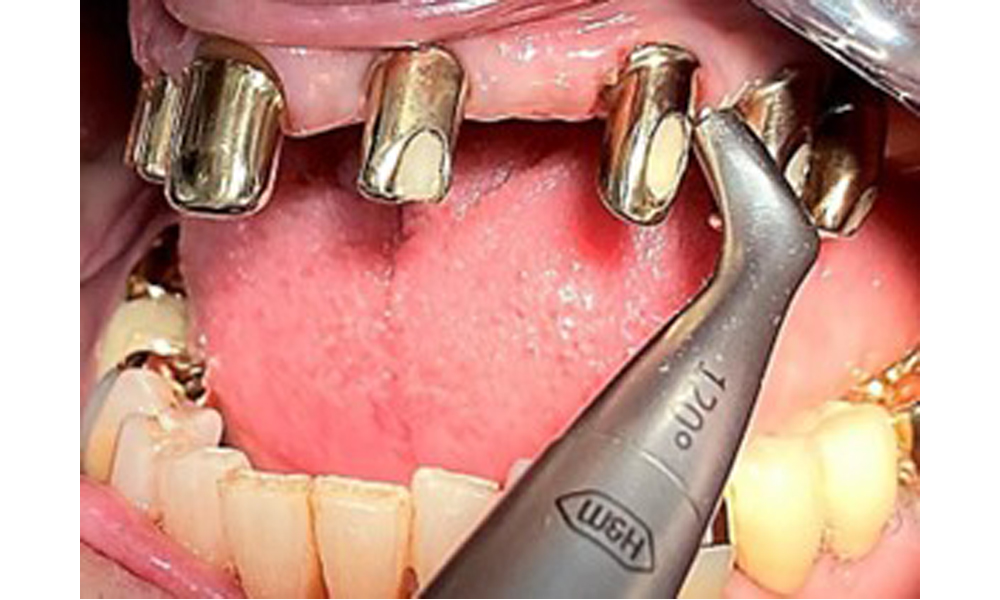

Occlusal view: Maxilla with tooth and implant-supported telescopic prostheses.

Fig. 2: Occlusal view: Maxilla with tooth and implant-supported telescopic prostheses

The dental findings are as follows: Combined removable implant and tooth-supported telescopic prostheses on implants 15, 13, 21, 23, 24, 25 and tooth 11 (Fig. 1, Fig. 2, Fig. 3). The patient was fitted with a fixed mandibular denture. Adequate bridges were present over 37 to 34 and 45 to 47 (Fig. 4), the crown margins were intact and there were no active caries. A composite filling with a marginal gap was present on tooth 43. There was mandibular gingival recession, exposing 1 to 3 mm of root surface. This also applies to 11.